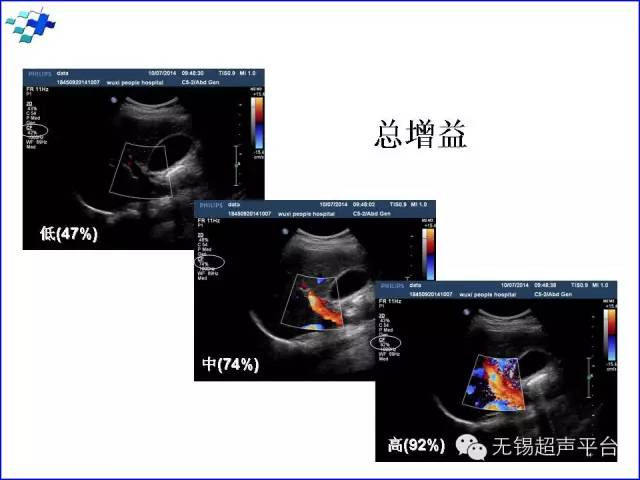

增益控制(gain control):彩色增益设置过低,则彩色信号显示困难。设置过高,会出现彩色外溢,混叠。